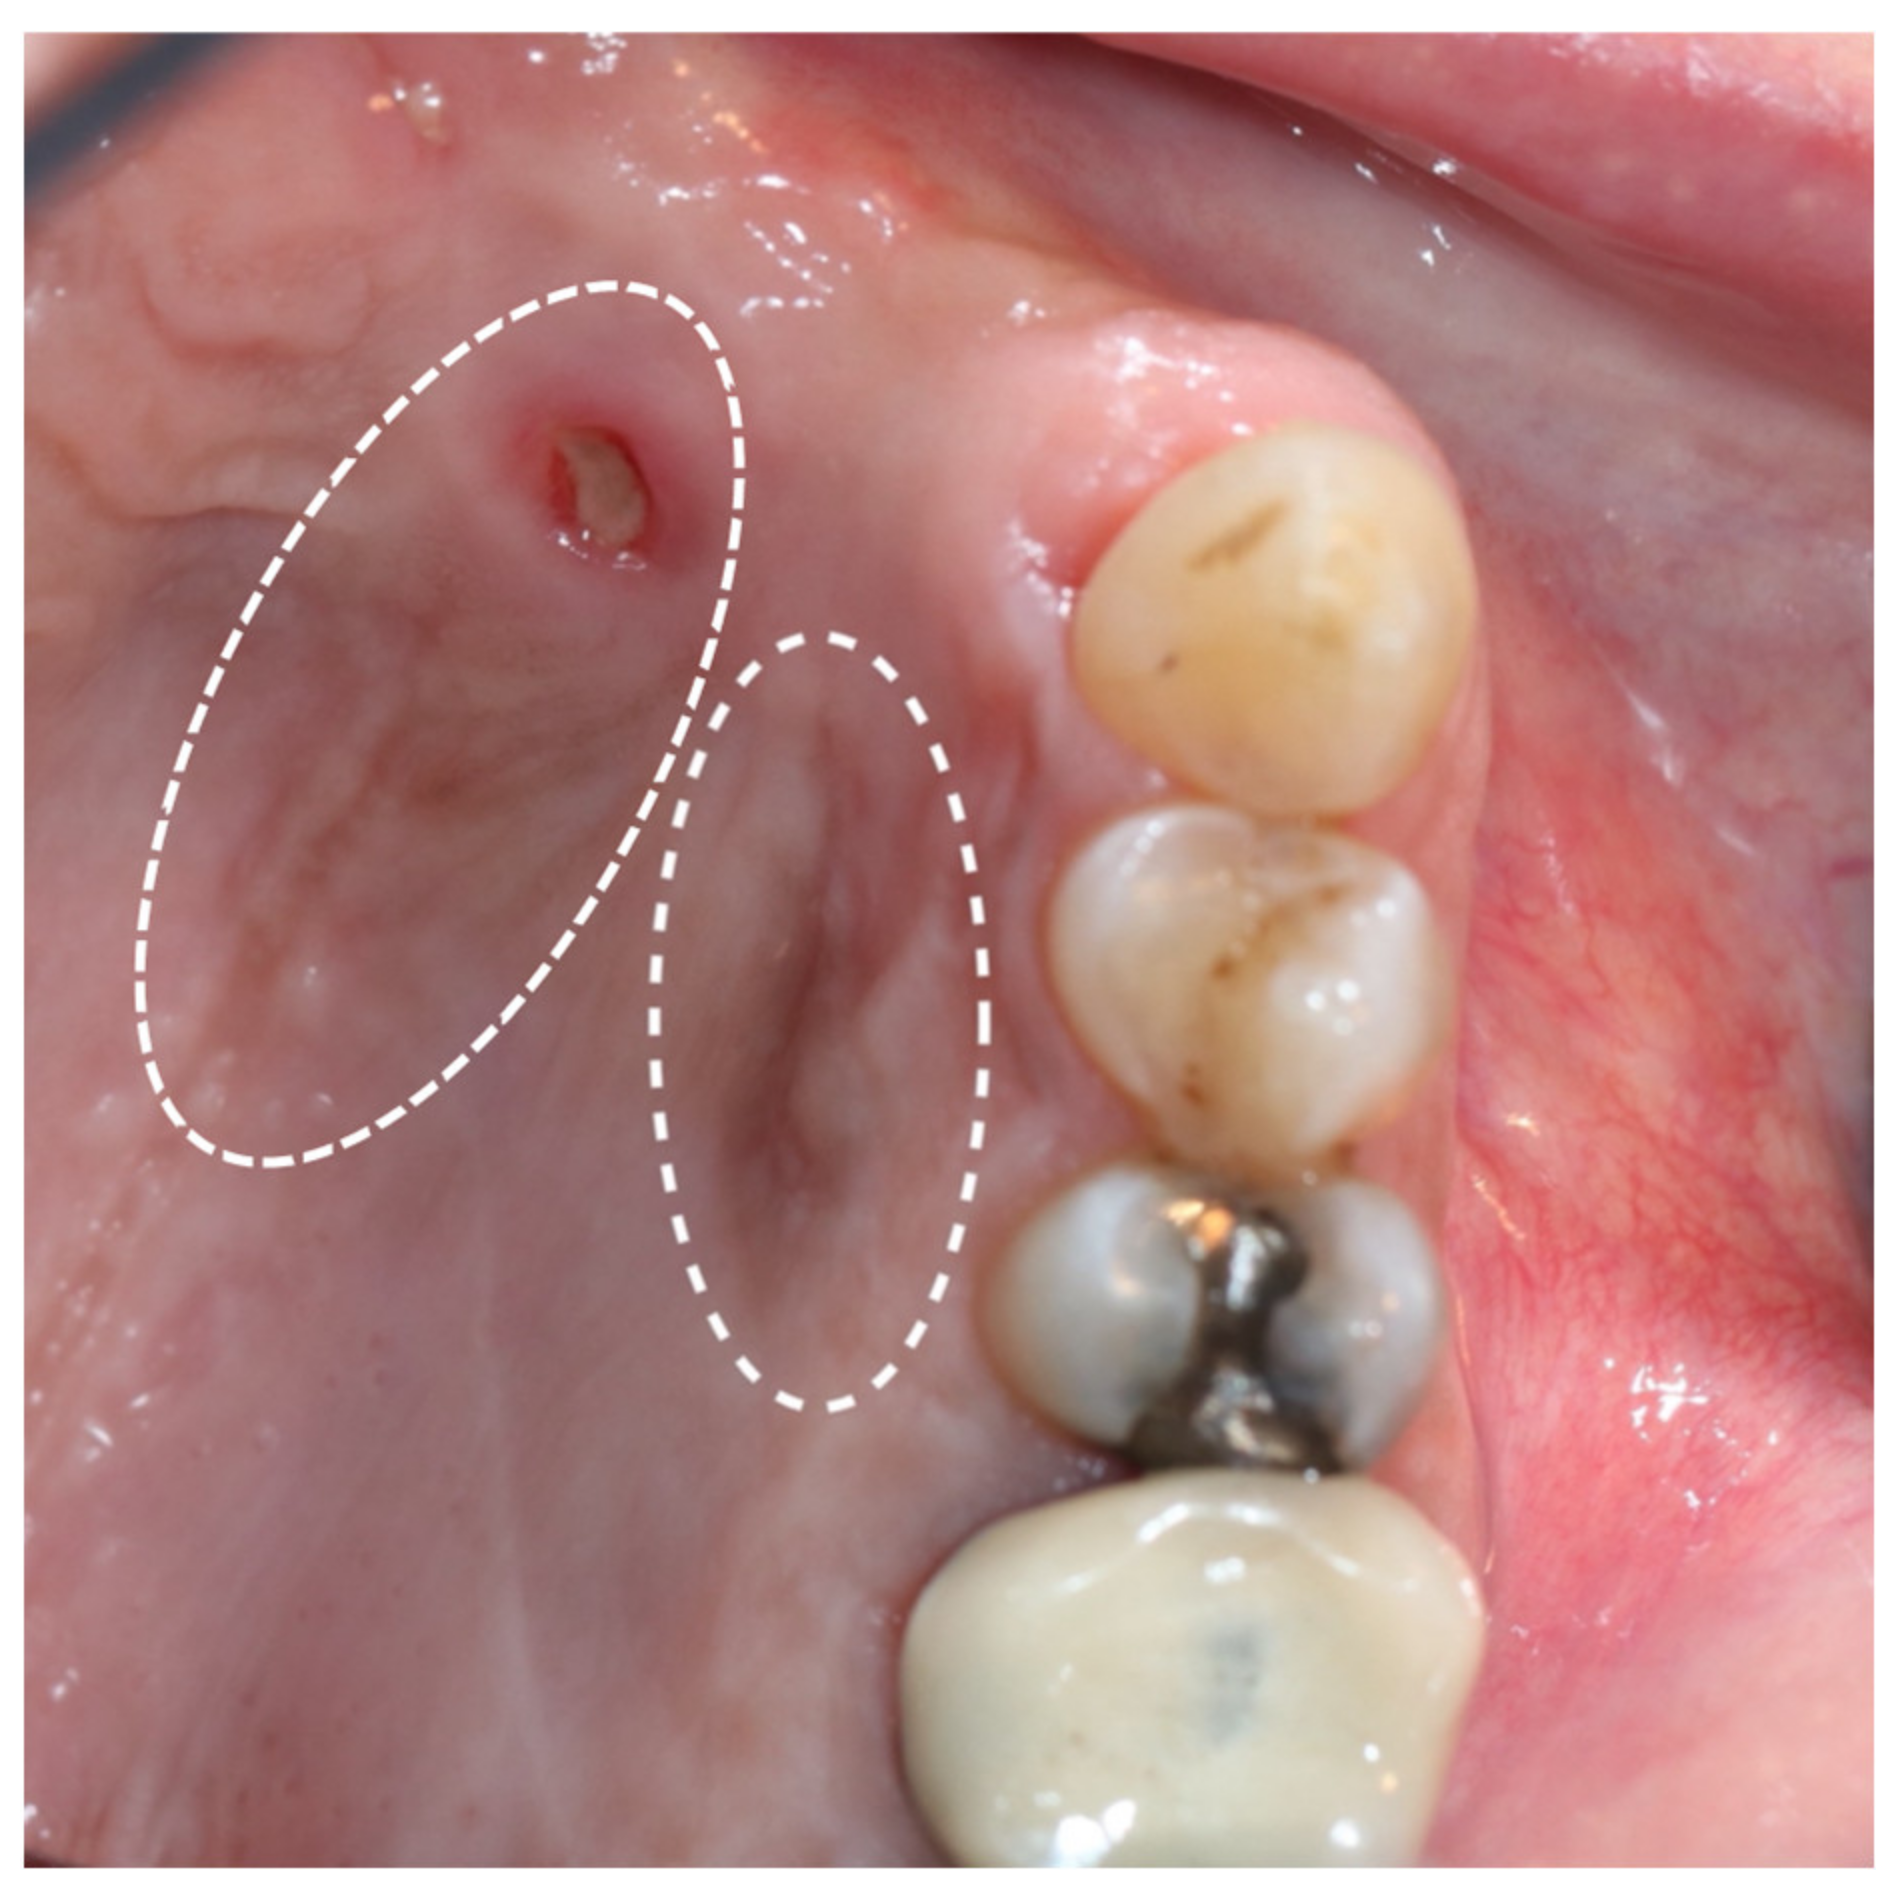

2. Case Report